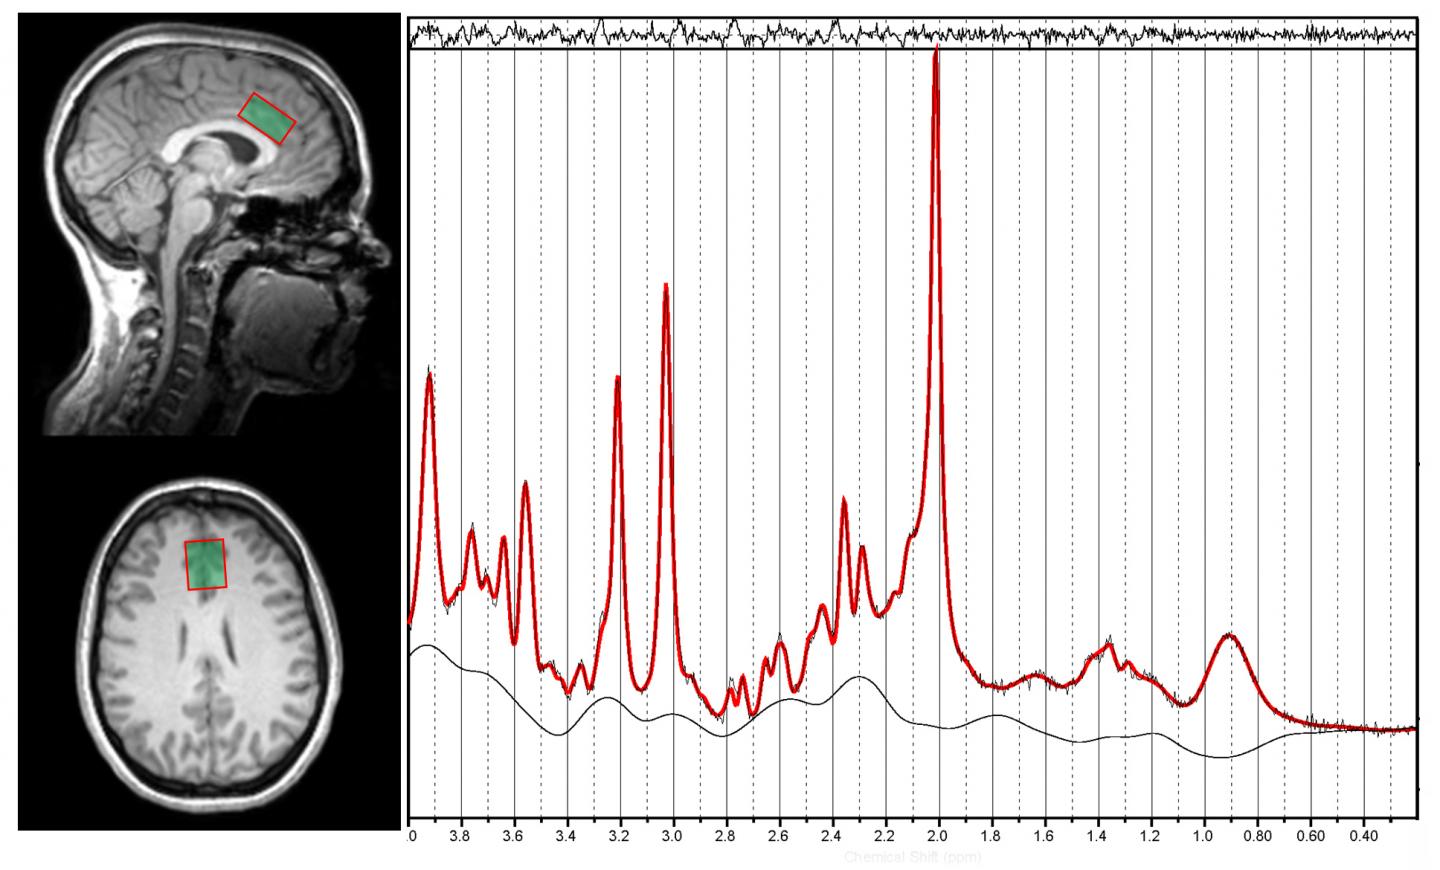

To conduct the new study, researchers enlisted 35 subjects, 17 with alcohol use disorder and 18 without the disorder. Then they measured concentrations of glutamate using a technology called magnetic resonance spectroscopy. The study found a decrease of the chemical in the brain of people with alcohol abuse disorder after they were shown cues associated with drinking -- such as a photo of alcohol in a glass -- compared to when they viewed neutral photos. Individuals without the disorder showed no change in glutamate levels when viewing the same images.

"We recognized we could measure glutamate levels in the human brain using magnetic resonance spectroscopy," said Newman, who led the collaboration between her department's addiction researchers to build upon Rebec's previous work in animals. "Scientists can now confidently target glutamate levels in the brain as they develop new treatments for alcoholism and other forms of addiction."

Technical expertise on the use of magnetic resonance spectroscopy to measure glutamate levels was provided by Newman, director of the IU Imaging Research Facility; Hu Cheng, a senior scientist in the Department of Psychological and Brain Sciences; and Ulrike Dydak, a professor in the School of Health Sciences at Purdue University. IU professor Peter Finn , a clinical psychologist who studies decision-making behavior in the early stages of alcohol use disorders, assisted in the recruitment of participants in the study.